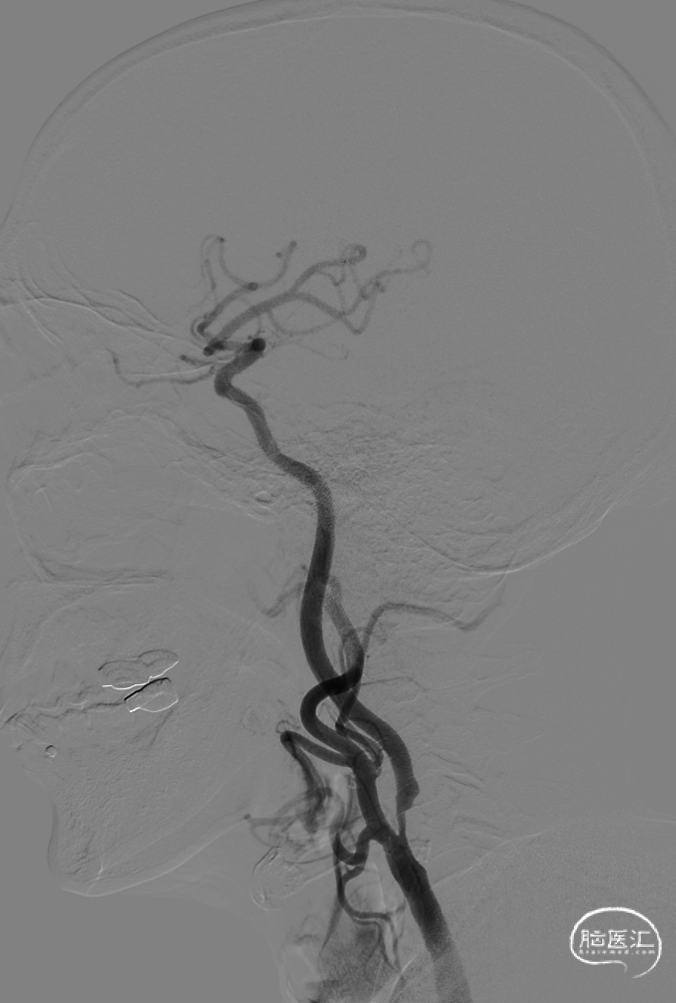

术后侧位造影:

术后正位造影:

小心缓慢释放支架,支架完全释放后手推造影,见支架位置良好,打开较好,原狭窄明显改善,残余狭窄20%。